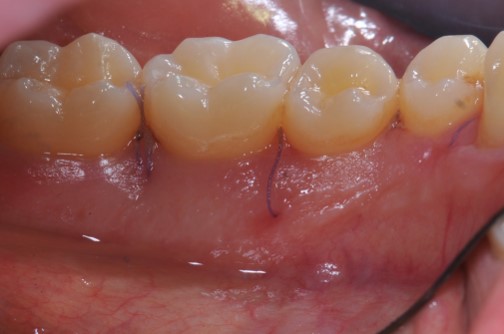

Radiographic view before periodontal regenerative therapy with Straumann® Emdogain®. A deep intrabony defect appeared mesially and distally on the left mandibular first premolar. Pre-surgical probing measured 8 mm. The defect morphology presented as well-contained.